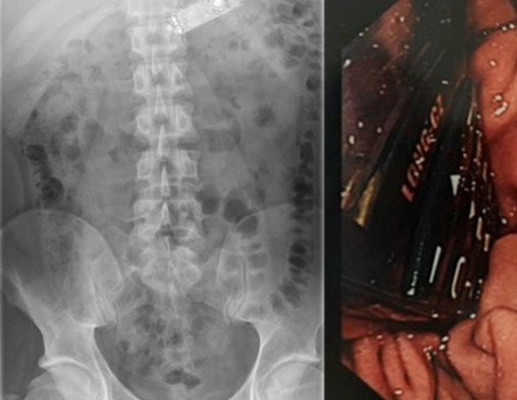

Ce au gasit gardienii in stomacul unui detinut dintr-o inchisoare irlandeza. L-au dus de urgenta la spital

Unora le e greu sa inghita micul dejun ori pranzul, in timp ce un detinut irlandez i-a socat pe gardieni.